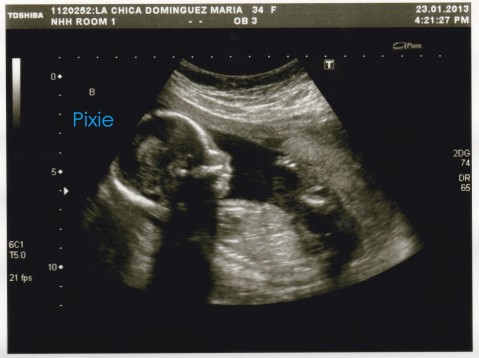

Here are the pictures that we got yesterday:

This is Pixie (top one)